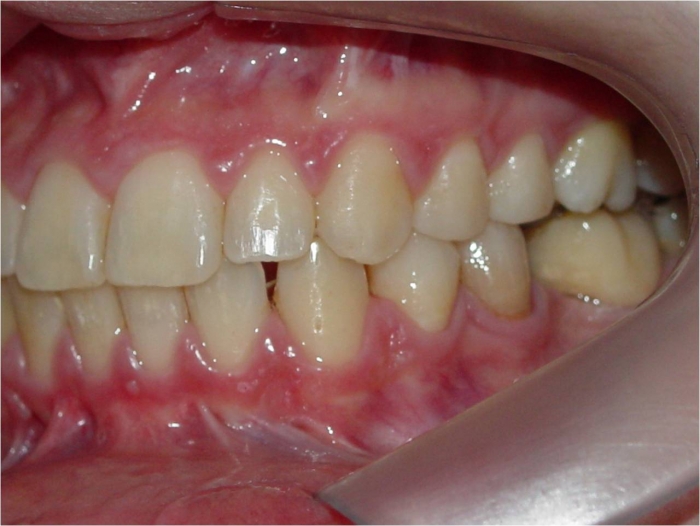

Mordida perfil inicial